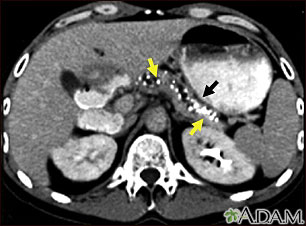

Imaging tests that can show swelling, scarring, calcifications or other changes of the pancreas may be seen on:

- CT scan of the abdomen